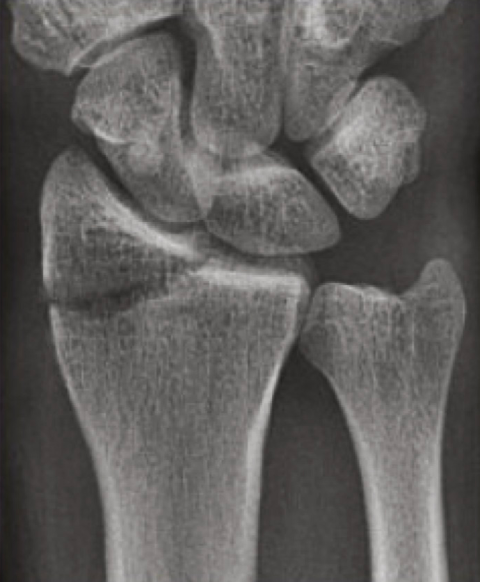

A radiografia de punho será crucial na avaliação inicial do paciente, sendo necessário as incidências póstero-anterior, perfil e oblíqua. Diversos parâmetros serão utilizados pelo cirurgião de mão para analisar a gravidade da fratura, sendo a radiografia do membro contralateral necessária em algumas situações. Da mesma forma, a

Parâmetros básicos radiológicos utilizados nas radiografias. A - Tilt volar, B - Inclinação radial, C - Variância ulnar.

Parâmetros radiográficos na incidência em perfil.